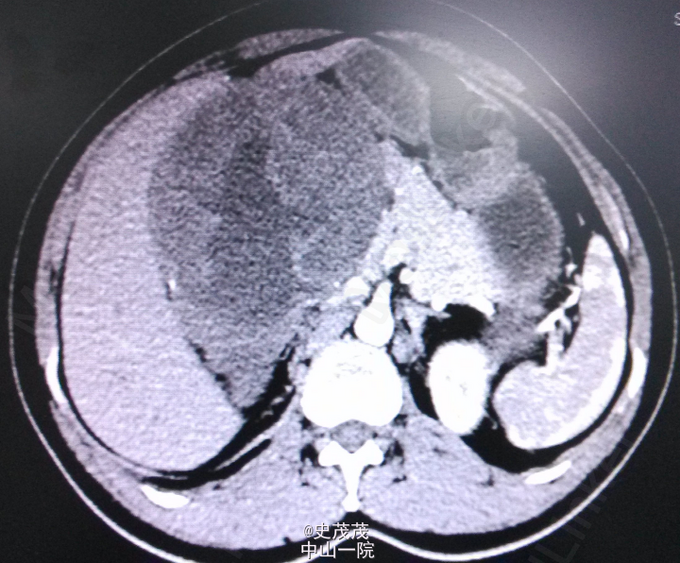

查体:生命体征平稳,发育正常,营养欠佳,双侧腰部对称无隆起,双肾未扪及,双肾区无叩痛,双侧输尿管行程及膀胱区无压痛、叩痛。.辅助检查: CT右肾见一低密度肿块影,边界尚清,大小约13.5cm×11.5cm×12.8cm,密度不均,内见更低密度影,肿块边缘可见多发小钙化灶,增强动脉期肿块实性部分有轻度强化,静脉期有中度强化,内见无强化低密度区。考虑肿瘤,乳头状肾细胞癌可能